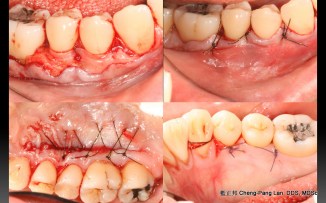

Root Coverage – Coronally Advcanced Flap with Connective Tissue Graft- Case B

Recipient Site: Harris’s technique, 1992

Donor Site: Bruno’s technique, 1994